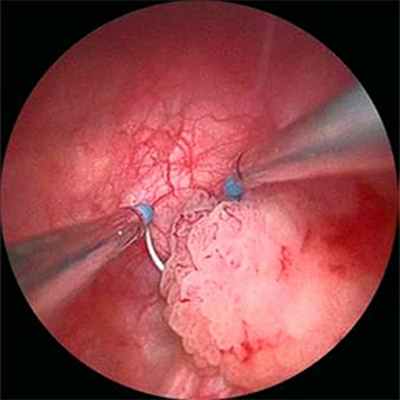

При поверхностных формах рака мочевого пузыря основным методом лечения является трансуретральная резекция (ТУР) стенки мочевого пузыря. Целью операции является удаление опухоли с лечебной и диагностической целью. В послеоперационном периоде с целью снижения риска рецидивирования рака мочевого пузыря проводится курс внутрипузырной химиотерапии или иммунной терапии (инстилляции химио или иммунных прапаратов в мочевой пузырь).

Ведущим методом диагностики рака мочевого пузыря является цистоскопия. Метод заключается в осмотре полости мочевого пузыря. При цистоскопии можно оценить состояние слизистой мочевого пузыря, размеры, количество, локализацию, внешний вид, распространенность опухоли, а также вовлеченность устьев мочеточников.

Трансуретральная резекция мочевого пузыря (ТУР). Хирургическая операция, при которой специальное оборудование вводится через уретру. Воздействие на опухоль производится путём резекции, лазером, электрокоагуляцией.

Основным методом лечения в такой ситуации является трансуретральная электрорезекция стенки мочевого пузыря с новообразванием (ТУР).

Эта методика имеет диагностическое и лечебное значение – она позволяет забрать материал для гистологического исследования (подтверждение диагноза) и удалить новообразование в пределах здоровых тканей. К сожалению, после ТУР стенки мочевого пузыря с новообразованием вероятность рецидива опухоли составляет в среднем 50%. Снизить этот процент позволяет использование фотодинамической диагностики и внутрипузырное введение вакцины БЦЖ или химиопрепаратов (митомицин, доксорубицин и др.). В фазе разработки находятся многообещающие методики внутрипузырного лекарственного электрофореза. После выполнения ТУР абсолютно ОБЯЗАТЕЛЬНО выполнять повторные контрольные осмотры мочевого пузыря для исключения рецидива. При многократных рецидивах после ТУР и обнаружении низкодифференцированного («злого») рака нередко бывает целесообразно прибегнуть к радикальной операции – цистэктомии (удаление мочевого пузыря) с формированием нового мочевого пузыря из сегмента кишки. Такая операция особенно эффективна при ранних формах рака и обеспечивает высокие онкологические результаты. При адекватном лечении 5-ти летняя выживаемость пациентов с поверхностным раком мочевого пузыря превышает 80%.